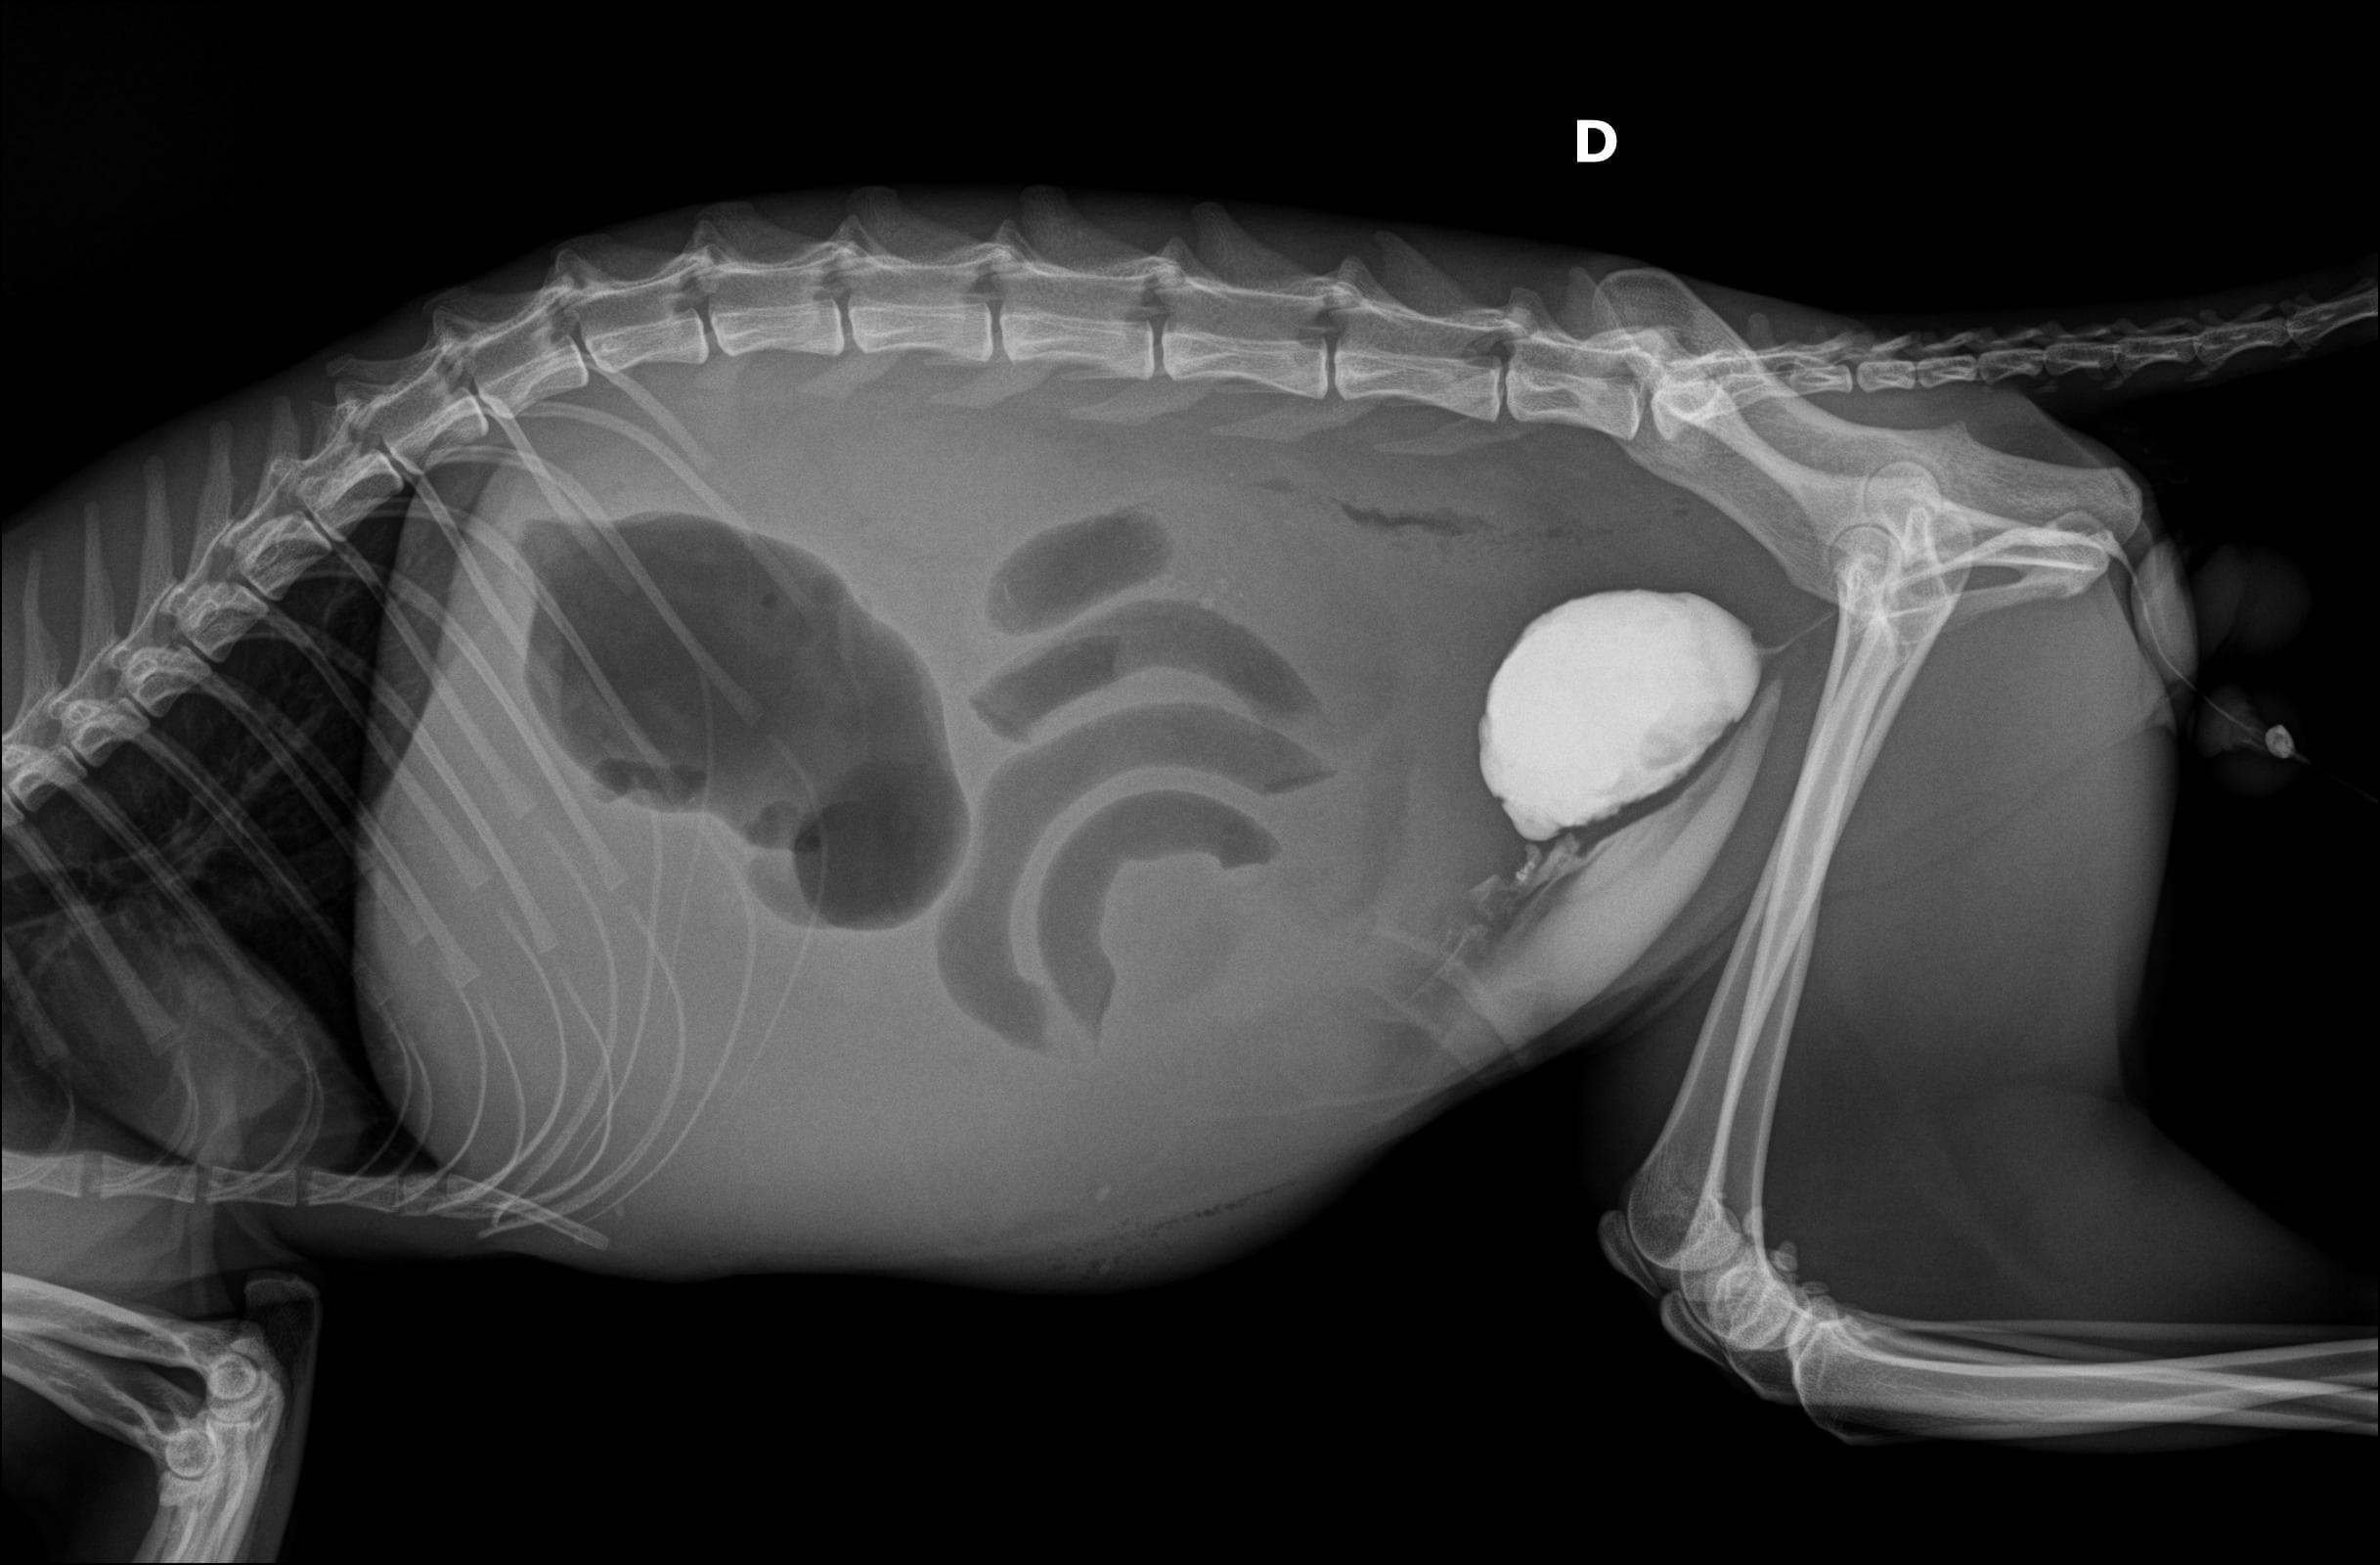

Nosso serviço de radiologia digital é projetado para oferecer diagnósticos precisos para cuidar da saúde dos pets. Contamos com equipamentos de última geração que nos permitem capturar imagens de alta qualidade e definição, fornecendo uma visão clara das estruturas. Essa tecnologia avançada nos permite identificar diversas condições médicas com maior precisão e detalhamento.

Além disso, a radiologia digital oferece a vantagem de resultados imediatos, facilitando a tomada de decisões rápidas e eficientes. Nossa equipe de profissionais trabalha com dedicação e cuidado para garantir o conforto e bem-estar dos pets durante o procedimento radiográfico.